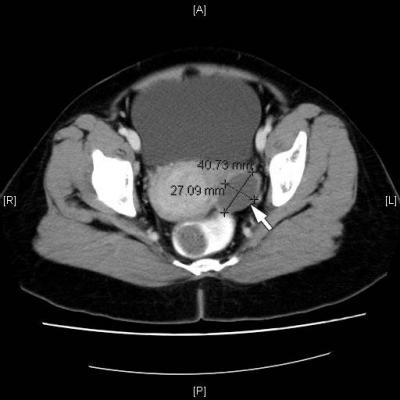

Primary Adenocarcinoma of the Fallopian Tube Mimicking Pelvic Inflammatory Disease

Tamby MR

,

Juliana MB

Wan Hamilton WH

Hemlata KG

Masir N

Related Terms:

diagnosis

fallopian tube carcinoma

pelvic inflammatory disease

Case report